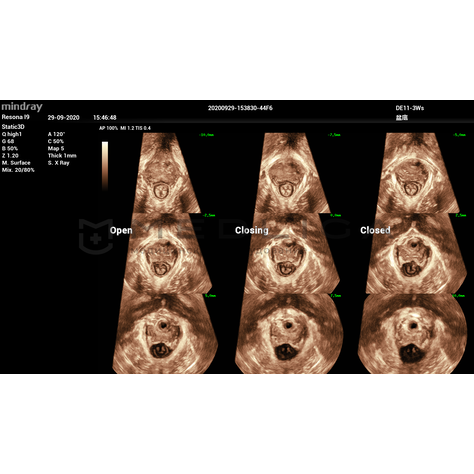

Программное обеспечение для автоматических измерений параметров и оценки функции мышц тазового дна.

Smart Pelvic - новое решение, позволяющее значительно упростить диагностическую процедуру и свести к минимуму время исследования функций мышц тазового дна. Благодаря чрезвычайно простому пользовательскому интерфейсу, программа генерирует стандартную систему координат и автоматически просчитывает все связанные измерения в течение нескольких секунд.